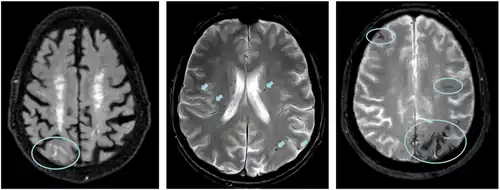

Mitte: ARIA-H (Mikroblutungen; T2*-Wichtung)

Rechts: ARIA-H (oberflächliche Hämosiderinablagerungen; T2*-Wichtung)

Amyloid-assoziierte Bildgebungsanomalien (ARIA) sind Unregelmäßigkeiten auf MRT-Bildern des Gehirns, die vor allem bei Einleitung oder Umstellung einer Therapie mit Anti-Amyloid-Antikörpern auftreten. Die Unterform ARIA-H repräsentiert kleine Blutaustritte, ARIA-E Flüssigkeitsansammlungen. Die Entstehung ist nicht vollständig verstanden, vermutlich kommt es durch einen Entzündungsprozess in den Blutgefäßen des Gehirns zu Schäden an den Gefäßwänden. Besonders häufig treten ARIA bei höheren Dosierungen und Menschen mit zwei Kopien der ApoE4-Variante oder Amyloid-Ablagerungen in den Blutgefäßen (zerebrale Amyloid-Angiopathie) auf. Meist handelt es sich um Zufallsbefunde, die keine Symptome verursachen, insbesondere ARIA-E kann durch die Schwellung jedoch zu Kopfschmerzen, Übelkeit und Verwirrungszuständen führen und einen Abbruch der Therapie erzwingen.[6]